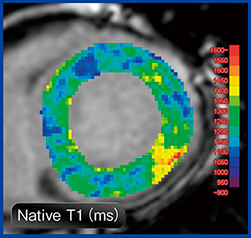

図2 MR心筋T1マッピングによる心筋評価:心ファブリー病

ファブリー病の家族歴あり。Native T1は不均一に短縮(カラーマップの青領域)しており,脂質沈着が示唆される。後側壁にはNative T1の延長(カラーマップの赤領域)があり,心筋線維化を生じていると考えられる。